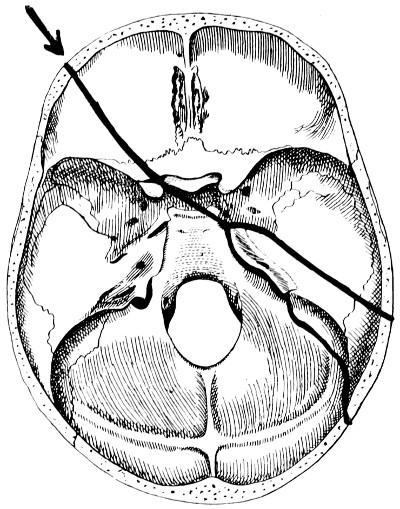

29 A and B. The base of the skull and the base as seen on transillumination 70, 71

30. Plan of the base of the skull 77

31. To illustrate the relation of basic fractures to cranial nerves 81

32-37. The lines pursued by basic fractures 83-8